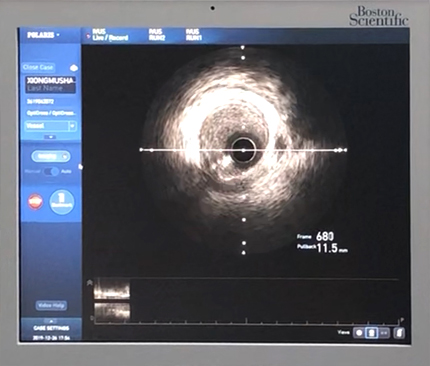

【血管内超声(IVUS)】

血管内超声是导管和超声技术相结合的产物,通过超声技术观察冠脉内壁的病理状态,如斑块纤维帽的厚度、支架贴壁情况等,还可以精确测量血管内径,使得支架的大小、长短选择更加精确,相对于X线下的影像学测量,可有效减少支架内再狭窄的发生率。